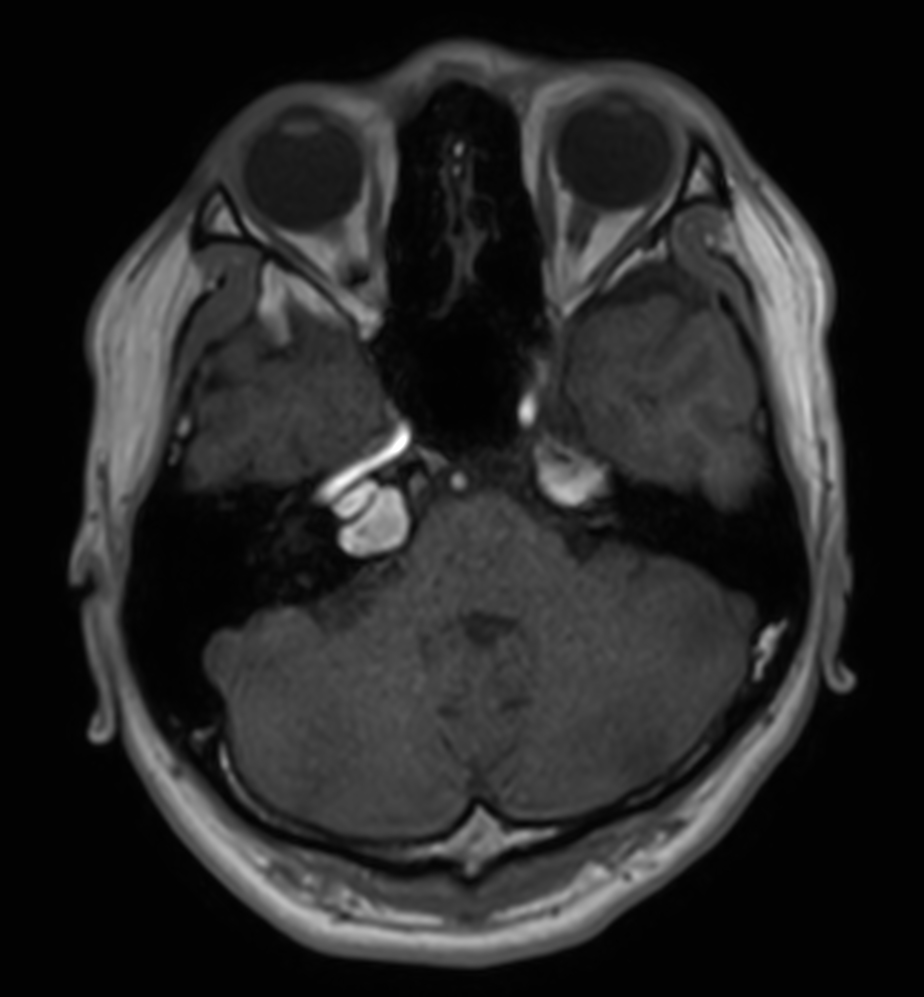

Patient with an IAC lesion. Comparing different DWI methods (EPI, TSE, ZOOM). Compressed SENSE is added to all TSE sequences to decrease scan times, thereby shortening the time the patient has to spent in the magnet. The dS Head 32ch coil is used to enhance image quality.

T2w TSE

T2w FLAIR